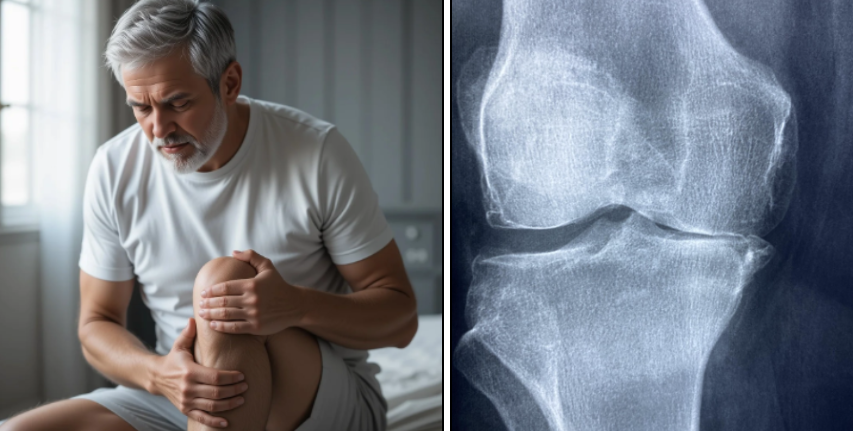

무릎 관절의 삼출액은 무릎 관절 내에 활막에서 분비되는 체액이 정상보다 과도하게 쌓여 발생하는 상태를 말하며, 흔히 "무릎에 물이 찼다" 또는 "무릎 부종"으로 표현됩니다. 활막은 관절낭을 덮고 관절을 원활하게 움직이게 하는 윤활액을 만드는 조직인데, 염증이나 부상 등으로 인해 이 활막에서 과도하게 체액이 생성되면서 무릎이 붓고 통증, 뻣뻣함, 운동 범위 제한 등의 증상이 나타납니다.

무릎 부기와 팽윤(부풀어 오름)

통증과 압통, 움직임 제한

뻣뻣함, 무릎을 굽히거나 펴기 어려움

무릎 부위 발적, 열감 (염증이나 감염 시)

체중 부하 시 통증으로 걷기 어려움